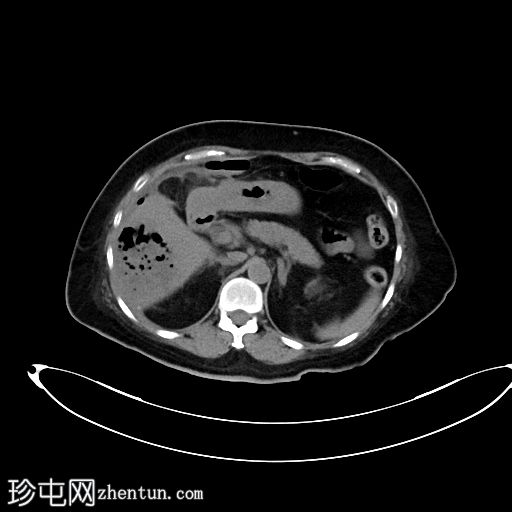

CT

轴位

非增强

4.jpg

肝段 6 和 7 可见多房性积液,呈环状强化

积液内可见多个气体腔

破入肝包膜下间隙,可见肝包膜下积液及气体腔

壁层腹膜与前腹壁之间可见另一局灶性积液

肝段 7 的肝内胆管局灶性扩张(0.3cm),内含气体腔

其他肝内胆管和肝外胆管均正常

胆囊缺失,可能由于既往胆囊切除术所致

无游离液体。

双侧肾皮质囊肿

轻度右侧胸腔积液伴邻近肺不张